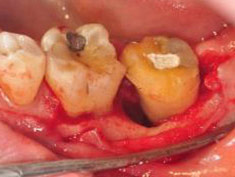

牙周初診時患者之口內觀。口內明顯牙菌斑及牙結石堆積。全口嚴重牙齦紅腫。治療前X光片。#37的近心側有較深的骨內缺損,剩餘齒槽骨高度只有20%。

第一階段牙周基本治療後,牙齦發炎狀況明顯獲得改善。